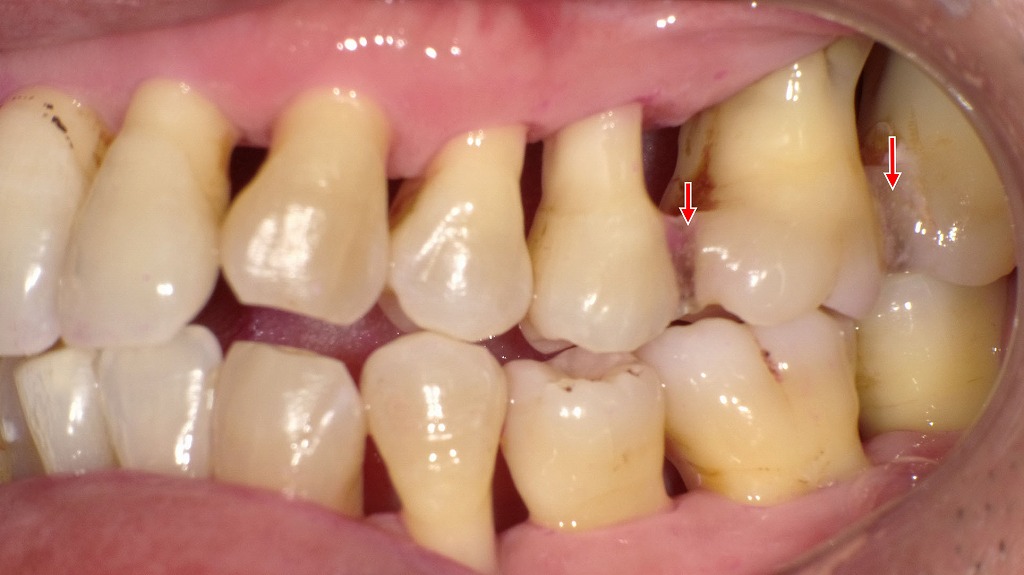

👀右側面観・左側面観

重度歯周病治療後の側面所見です。上顎臼歯部には歯の動揺を抑える目的で暫間固定(T-FIX)を行っています。歯周治療により炎症が改善し、歯ぐきの腫れが引いた結果、特に上顎臼歯部で歯肉退縮と歯根面の露出が明瞭に認められます。現在はプラークコントロールが良好で、定期的なクリーニングにより歯周組織は安定した状態を維持しています。